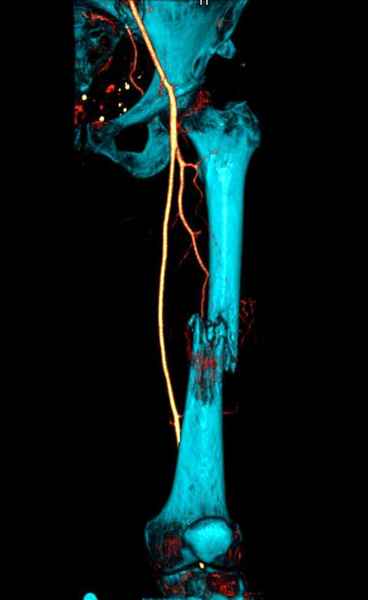

Со слов, больная ничем не болела, только последние 3 месяцев чувствовала боли в бедренной области. КТ брюшной полости подтвердил увеличенную правую почку. (5-6)

Для предупреждения кровотечения во время рассверливания, за день до операции провели эмболизацию сосудов питающий метастаз. http://radiology.rsnajnls.org/cgi/reprint/150/3/673.pdf (7-11, 12-15-16)

С минимальным рассверливанием и ретроградным методом провели остеосинтез бедра 12 мм гвоздем. (17-20)

Кровопотеря во время операции меньше 100 мл.